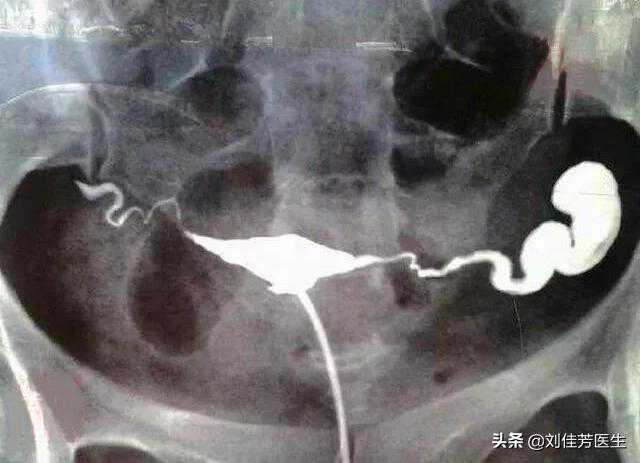

输卵管积水后,备孕的你要知道的风险,或致流产率增加

对女性来说,面临的最大健康威胁之一,肯定少不了妇科疾病。妇科...